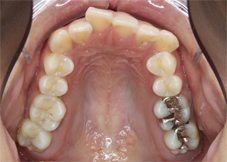

前歯のでこぼこと八重歯を気にされて来院されました。

左上の犬歯がかなり上から生えてきて八重歯になっています(左写真)。前歯の脇の歯は内側に入ってしまい前歯がでこぼこで、どちらの歯も磨きにくく汚れがたまりやすい状態です。

特に八重歯の状態は他の歯より上に位置するため磨き残されやすく、虫歯にしてしまいがちなので要注意です。

<治療開始前>

左上の犬歯が八重歯になっており、そのため上真ん中は大きく左へズレています。また本来、上の前歯は下の前歯に覆いかぶさらないといけないのですが、上下前歯は咬み合っていません。

<治療開始6ヶ月後>

歯が並ぶスペースが著しく不足しているためこれを解消すること、また上下の咬み合っていない前歯の状態を解消するために上下とも抜歯を行い治療を開始しました。治療開始から6ヶ月後、八重歯は改善しています。この後、上下の噛み合わせの改善を行いました。

<矯正治療後>治療期間22ヶ月

22ヶ月後、歯の移動を終了して装置を除去、保定に入りました。装置は表側の装置ですが目立ちにくいタイプのもの使用しています。材質はサファイアで透明度が高いため歯の色と馴染むのが特徴です。ワイヤーはホワイトワイヤーを使用してさらに目立ちにくくしています。